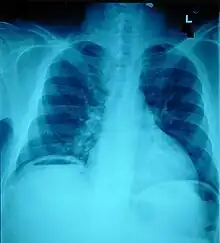

The small intestine takes up a large part of the abdomen and is likely to be damaged in penetrating injury.[5] The bowel may be perforated.[4] Gas within the abdominal cavity seen on CT is understood to be a diagnostic sign of bowel perforation; however intra-abdominal air can also be caused by pneumothorax (air in the pleural cavity outside the lungs that has escaped from the respiratory system) or pneumomediastinum (air in the mediastinum, the center of the chest cavity).[4] The injury may not be detected on CT.[4] Bowel injury may be associated with complications such as infection, abscess, bowel obstruction, and the formation of a fistula.[4] Bowel perforation requires surgery.[4]

Ten percent of people with polytrauma who had no signs of abdominal injury did have evidence of such injuries using radiological imaging.[1] Diagnostic techniques used include CT scanning, ultrasound,[1] and X-ray.[7] X-ray can help determine the path of a penetrating object and locate any foreign matter left in the wound, but may not be helpful in blunt trauma.[7] Diagnostic laparoscopy or exploratory laparotomy may also be performed if other diagnostic methods do not yield conclusive results.[5]